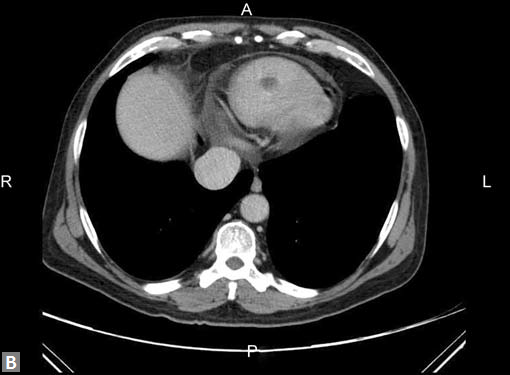

The most common mass lesion in heart is thrombus. Postinfarct clot is common in LV apex. Postinfarct aneurysm of LV may have clot. Rheumatic mitral valve disease with AF has left atrial (LA) appendage thrombus. Large one can extend to body of thrombus. Patients with arrhythmogenic right ventricular dysplasia (ARVD), sarcoidosis can have thrombus in right ventricle. SVC and IVC thrombus can extend to right atrium. Long-standing catheters can be source of thrombus in innominate veins and SVC.

Carcinomas of liver, kidney can directly extend to IVC and then into RA.

Site of the mass and prevailing clinical scenario help to differentiate the clot from neoplasm, although it may not be possible to do the same definitively.

Clots are more likely to have calcific foci (Figs 21I to K) within when they are long standing. Neoplasms with signifi cant neoangiogenesis show discernible contrast enhancement.

This phenomenon is better seen with MRI contrast than with CT contrast. Exceptionally, vascularized throm bus can show contrast enhancement.

Mass lesion in left atrium with ball valve movement is a myxoma (Fig. 21L). Most commonly located near fossa ovalis of interatrial septum (IAS). Multiple myxomas are seen in

Carney’s complex. Calcification may be present. LA myxomas are pedunculated and RA ones are generally sessile.